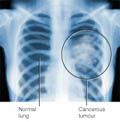

Πρωτεΐνη το κλειδί του μυστηρίου στον καρκίνο των πνευμόνων

Λονδίνο: Μια μόνο πρωτεΐνη ίσως είναι η λύση στην αποτελεσματική αντιμετώπιση του καρκίνου των πνευμόνων, σύμφωνα με αμερικανική μελέτη που δημοσιεύεται στο επιστημονικό έντυπο British Journal of Cancer.